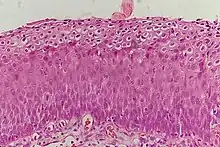

Classification

Historically, abnormal changes of cervical epithelial cells were described as mild, moderate, or severe epithelial dysplasia. In 1988 the National Cancer Institute developed "The Bethesda System for Reporting Cervical/Vaginal Cytologic Diagnoses".[12] This system provides a uniform way to describe abnormal epithelial cells and determine specimen quality, thus providing clear guidance for clinical management. These abnormalities were classified as squamous or glandular and then further classified by the stage of dysplasia: atypical cells, mild, moderate, severe, and carcinoma.[13]

Depending on several factors and the location of the lesion, CIN can start in any of the three stages and can either progress or regress.[1] The grade of squamous intraepithelial lesion can vary.

CIN is classified in grades:[14]

| Histology Grade | Corresponding Cytology | Description | Image |

|---|---|---|---|

| CIN 1 (Grade I) | Low-grade squamous intraepithelial lesion (LSIL) |

|

| CIN 2/3 | High-grade squamous intraepithelial lesion (HSIL) |

| CIN 2 (Grade II) |

| CIN 3 (Grade III) |